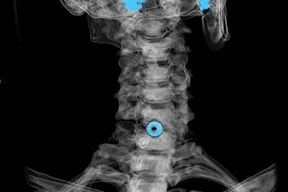

Diagnoos tehakse iseloomulike sümptomite põhjal, samuti kasutatakse:

- röntgenikiirgus. Meetod on ebaefektiivne, eriti osteokondroosi arengu viimastel etappidel.

- Emakakaela lülisamba MRI (magnetresonantstomograafia). Meetod, mis võimaldab näha luustruktuure, herniaalseid lülivahekettaid, nende suurust ja arengusuunda.

- Kompuutertomograafia. Vähem efektiivne lahendus kui MRI, kuna hernia olemasolu ja suurust on raske kindlaks teha.